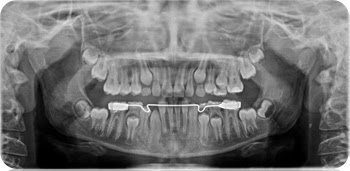

Digital radiography

2011 was revolutionary for our practice as we decided to switch over from analogue radiography to digital radiography. Our aim was to provide all our clients with quality treatment with low dose radiation exposure. At Sheppard Jane Dental Clinic, radiographs are prescribed by the dentists as per individual needs.